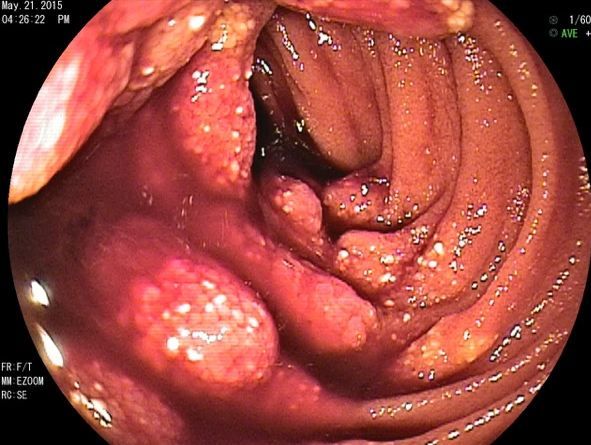

Figure 2. Mid-jejunum polypoid lesions with engorged, oozing villi seen on DBE.

Given the recent negative findings from the colonoscopy and EGD he was sent for a capsule endoscopy study. The capsule study showed a lesion in the jejunum and he was referred for a push endoscopy. Unfortunately, the lesion could not be reached for biopsy but was tattooed on push endoscopy. It was decided that the patient should undergo a double balloon enteroscopy (DBE) and he was temporarily transferred to one of the few facilities where this procedure was being performed. The DBE showed multiple lesions and masses in the jejunum (Figures 1-3; click to enlarge). The lesions could not be biopsied because they were so friable. The patient underwent CT scan of the abdomen/pelvis with contrast which showed multiple mesenteric nodules or mass lesions with the largest measuring up to 5 cm in the upper abdomen. Surgery was consulted and the patient was sent for small bowel resection; a 20-cm portion of small bowel was removed. There were multiple areas of mesentery with large masses. The resected bowel was sent to pathology. The pathology report provided a definitive diagnosis of lymphangiomatosis (plural of lymphangioma) of the small bowel and mesentery. The patient was subsequently referred to lymphangioma specialists at an out-of-state academic center for lymphangiogram studies.